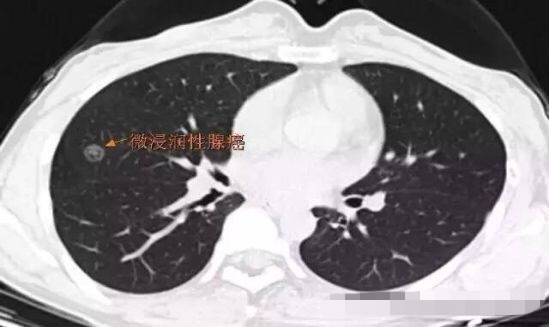

病例4

2013年发现, 每年随访,随访至2016年,病灶逐步增大,2013年5毫米大小,2016年11毫米,3年生长6毫米,平均每年2毫米